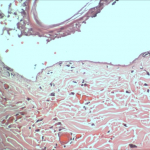

- Histopathology, by our in-house histopathology lab

- Immunohistochemistry

- Histomorphometry/digital image analysis